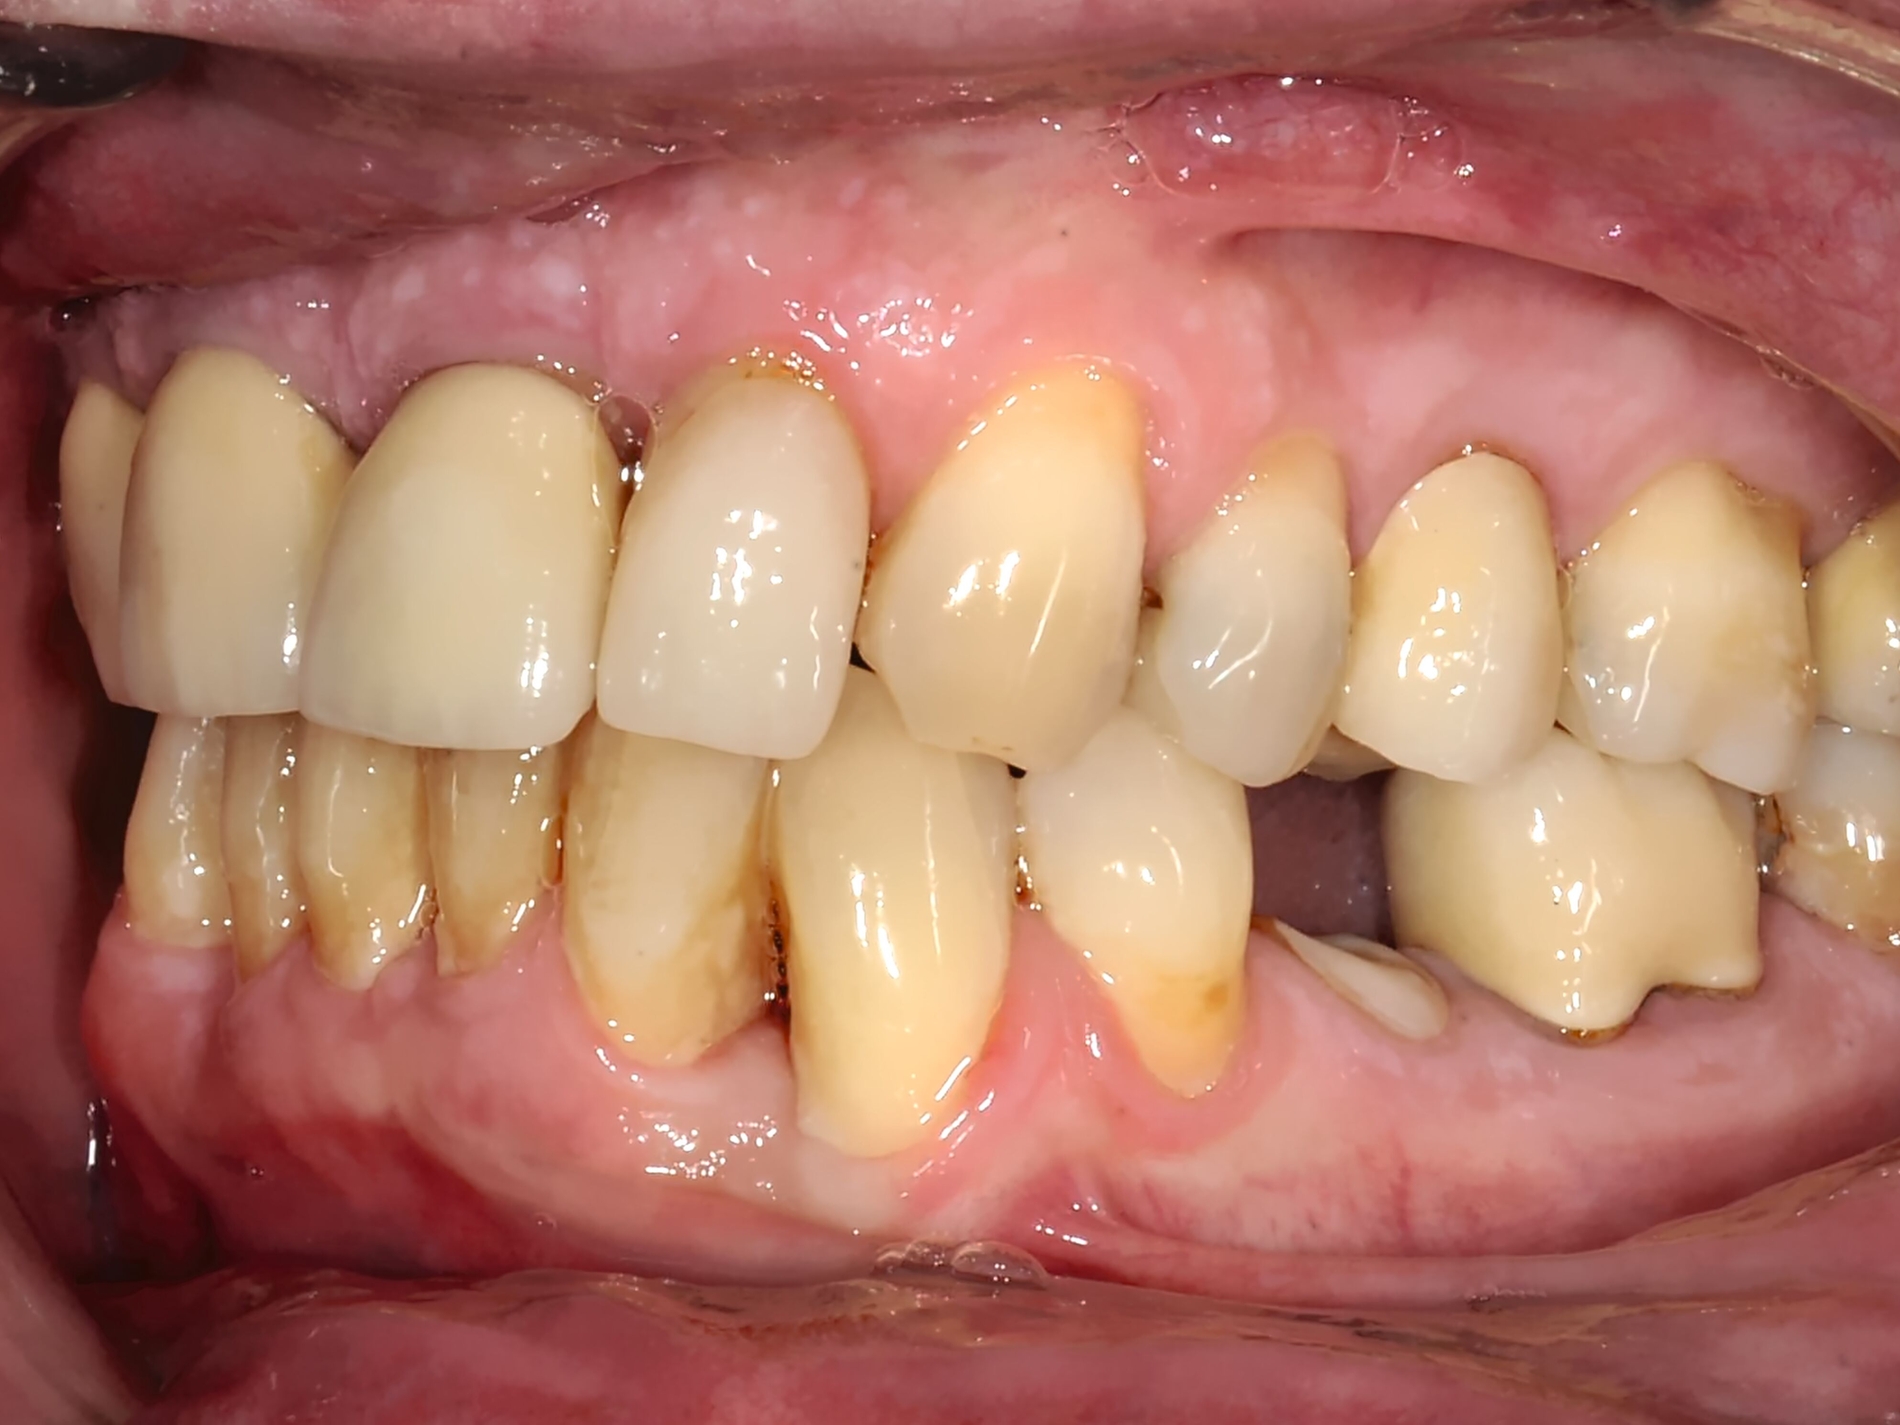

Gerade Patienten mit einer stark vergrößerten Frontzahnstufe und einer fehlenden Lippenbedeckung der Schneidezähne können von einer frühzeitigen kieferorthopädischen Korrektur vor der zweiten Wechselgebissphase profitieren [Bauss et al., 2008]. Malokklusionen erhöhen das Risiko für traumatische Zahnverletzungen [Bauss et al., 2008; Corrêa-Faria et al., 2016; O'Mullane, 1973]. Eine kieferorthopädische Behandlung für Kinder mit solchen Merkmalen (Abbildung 1) könnte daher hilfreich sein, um Frontzahntraumata sowie die daraus resultierenden Spätfolgen zu verhindern.